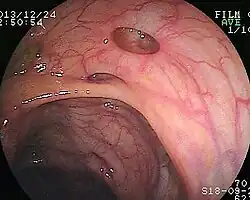

| Diverticulosis as seen endoscopically | |

Diverticulosis is the condition of having multiple pouches (diverticula) in the colon that are not inflamed. These are outpockets of the colonic mucosa and submucosa through weaknesses of muscle layers in the colon wall.[1] Diverticula do not cause symptoms in most people.[2] Diverticular disease occurs when diverticula become clinically inflamed, a condition known as diverticulitis.[3]

Diverticula typically occur in the sigmoid colon, which is commonplace for increased pressure. The left side of the colon is more commonly affected in the United States while the right side is more commonly affected in Asia.[4] Diagnosis is often during routine colonoscopy or as an incidental finding during CT scan.[2]

Diverticulosis is defined by the presence of multiple pouches (diverticula) in the colon.[22] In people without symptoms, these are usually found incidentally during other investigations.

- Colonoscopy will show the diverticulum and rule out malignancy. A colonoscopy should be performed 4–6 weeks after an acute episode.